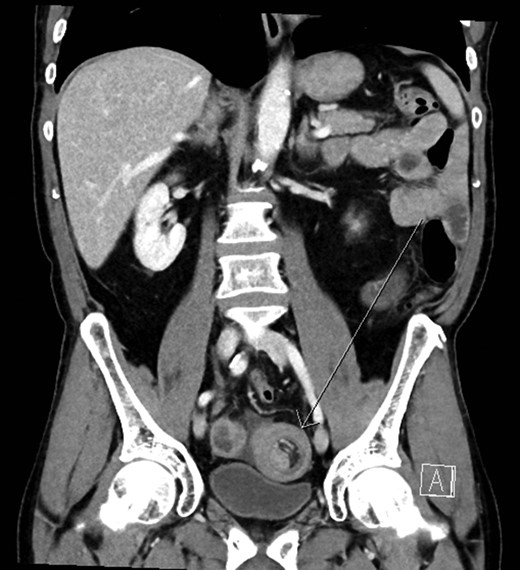

He had arterial hypertension and dyslipidaemia. Prior to this admission he had undergone oesophagogastroduodenoscopy and colonoscopy due to abdominal pain and anaemia. Oesophagogastroduodenoscopy showed erosive gastritis, colonoscopy showed diverticulosis of the sigmoid colon. Laboratory tests showed anaemia (haemoglobin 9 g/dL) and a mildly elevated C-reactive protein (68 mg/L). A plain abdominal X-ray showed air-fluid levels of the small intestine and abdominal ultrasonography confirmed intussusception of the small intestine and developing small bowel obstruction. Computerized tomography showed small bowel obstruction with dilated small bowel loops due to ileo-ileal intussusception (Fig. 1).

Abdominal CT scan ileo-ileal intussusception with a target sign (arrow).